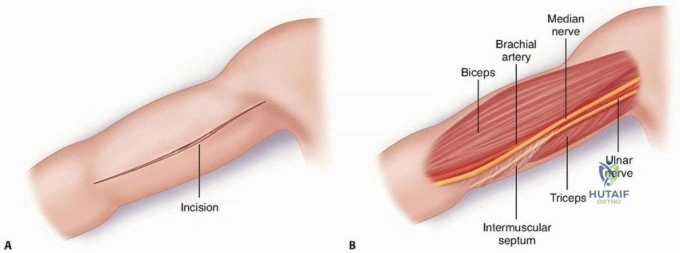

The Anterolateral Approach

The skin incision is made along a line connecting the coracoid process to the lateral epicondyle of the humerus. The length of the incision is dictated by the fracture pattern and the templated plate length. Subcutaneous tissues are dissected, taking care to identify and protect the cephalic vein, which can be retracted either medially or laterally depending on the exact proximal extent of the exposure.

The deep fascia is incised in line with the skin incision. The biceps brachii muscle is identified and mobilized medially, exposing the underlying brachialis muscle. At this juncture, the surgeon must decide on the specific handling of the brachialis muscle based on the fracture location.

For midshaft fractures, the brachialis muscle is split longitudinally down its midline. Because the medial half is innervated by the musculocutaneous nerve and the lateral half by the radial nerve, this longitudinal split is an internervous plane that preserves the function of both segments. The split is carried down to the periosteum, and the muscle halves are elevated off the anterior humerus. The lateral half of the brachialis acts as a protective muscular cushion between the retractor (and subsequently the plate) and the radial nerve.

For distal third fractures, the exposure must transition to the interval between the brachialis and the brachioradialis. The radial nerve emerges from the posterior compartment by piercing the lateral intermuscular septum and travels distally in the cleft between the brachialis (medially) and the brachioradialis (laterally).

To safely exploit this interval, the fascia between the brachialis and brachioradialis is carefully incised. The radial nerve must be actively identified and protected. It is often easiest to identify the nerve distally where the interval is wider and trace it proximally to where it pierces the septum. Once identified, the nerve is gently mobilized and protected with vessel loops. Retraction of the nerve must be minimal and meticulous to prevent iatrogenic neuropraxia.